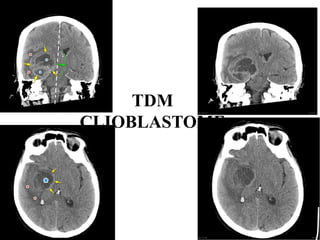

• GLIOBLASTOME: Tumeur gliale de haut grade

• TDM: Masse hypodense intra axiale hétérogène par la

présence de calcifications ou d’hémorragie intra

tumorale

• Rehaussement hétérogène

• Œdème péri lésionnel important avec Effet de masse

• IRM: examen clé+++.

• Etude multiplanaire en séquences pondérées

T1,T2,T2flair,T2*,T1gado(séquences morphologiques).

Séquences fonctionnelles++++: diffusion+calcul

de l’ADC/Tenseur de

diffusion/perfusion/spectroscopie. Signal

hétérogène :hyposignal T1hétérogène(Hgie),

hypersignalT2 hétérogène et Flair ( kyste,

nécrose). Prise de contraste hétérogène avec

remaniement hémorragique+++

Spectro:↑Pic de choline+↓Pic de NAA

Intérêt de l’IRM: dg positif et topographique.

Dgétiologique. Bilan d’extension des lésions

malignes . Guider la biopsie stéréotaxique ainsi

que le suivi

TDM

CLIOBLASTOME

Tm gliale haut grade:

GLIOBLASTOME